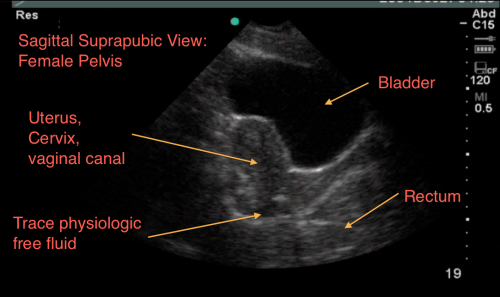

The Suprapubic Views

The suprapubic view on the eFAST exam is generally the last of the four views performed.

Both Longitudinal & Transverse views are required

Anatomically, when we scan the suprapubic area in both transverse and longitudinal planes, there’s a lot that we see –the bladder, bowel, pelvic bones, pelvic organs, and rectum to name a few.

This might make it harder for us to visualize free fluid, and separate it out from these other structures. But here’s a few tips to help overcome these limitations. Begin by placing your curvilinear probe just above the pubic symphysis, aiming inferiorly/caudad into the pelvis.

c. Look deep/posterior to the bladder between it and your pelvic organs.

Click Here for Free Fluid Posterior to the Bladder.

Especially in females, you can see a collection of free fluid between the bladder and the uterus. This often looks like boxed shaped anechoic structures that as you fan through will appreciate it not being a “contained” structure.

d. Look posterior to your pelvic organs. Free fluid can collect deep to your uterus or prostate.

6. Physiological free fluid in females - In menstruating females you can appreciate some physiological free fluid that may be normal.

This is hard to differentiate truly from traumatic free fluid, and you will need to consider the clinical picture – Is there any abdominal pain? Is there abdominal or pelvic trauma? Are her vital signs abnormal?

Also, the amount and location of free fluid can help – physiological free fluid is found deep to the uterus, and along its border – it should not be greater than 1/3 the length of the border, anything greater than 1/3 should be considered pathological.